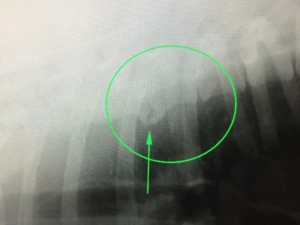

今回ご紹介したいのは背骨の病気のなかでも、老犬の健康診断で良く見つかる病気、変形性脊椎症についてご説明したいと思います。

変形性脊椎症はその名の通り、その脊椎が変形する病気です。

老齢性の変化としてとらえられており、基本的には犬種によっても発生率は異なりますが、ほぼすべての犬種において年齢を重ねると出てくる症状です。

変形した脊椎の個所は安定性が失われやすくなります。

たいていの場合は無症状なのですが、安定が失われた脊椎は時折炎症や痛みなどがでやすいため、背を丸めて歩いたり、触ると嫌な顔をしたりすることがます。

ぼく自身の経験上、老齢の日本犬のMIXや比較的体形が大柄な犬にみられることが多く、また体の真ん中あたりの脊椎で発生することが多いと思います。